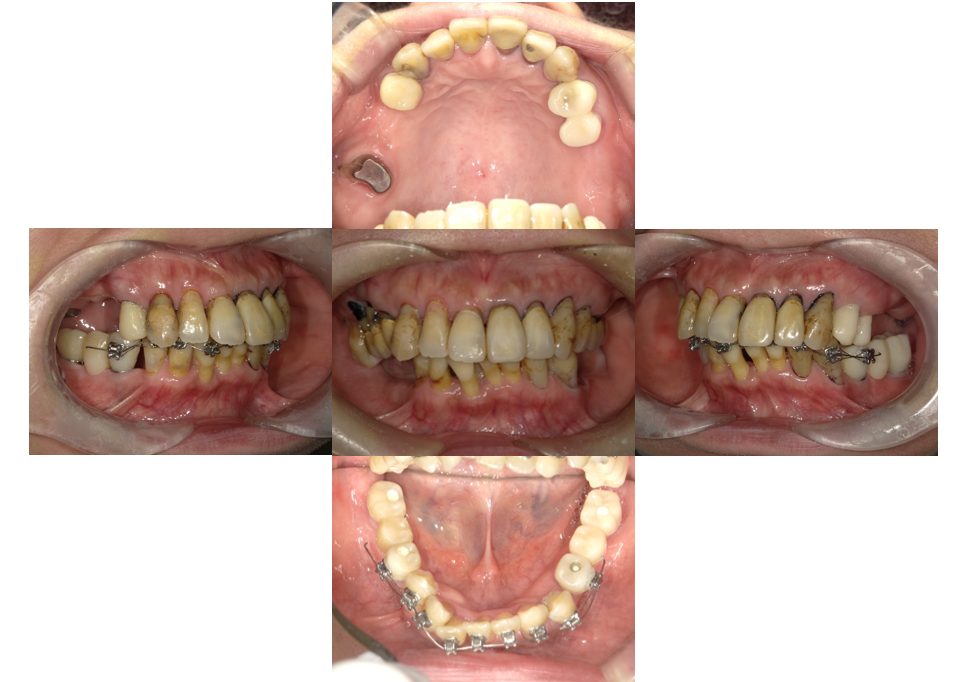

| 主訴 | 30代女性 顎関節が痛い。見た目も気になる |

| 治療内容 | 矯正治療を行いました。 |

| 治療費 | 1,700,000円(税込み) |

| 治療期間 | 3年(矯正治療期間 2年半) |

| 治療回数 | 40回 |

| 想定されたリスク | 術前に精密な診査診断とシミュレーションを行い、インプラントを適正なポジションに埋入しておかないと、インプラント自体が矯正治療の邪魔になるリスクがあった。 |